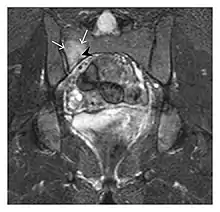

Occult osseous injuries may result from a direct blow to the bone by compressive forces of adjacent bones against one another or by traction forces during an avulsion injury. Lesions in the tibial plateau, hip, ankle, and wrist are often missed. In a tibial plateau fracture, any disruption of the posterior and anterior cortical rims of the plateau should be sought. Impaction of subchondral bone will appear as an increased sclerosis of the subchondral bone (Figure 1). In the hip, posterior acetabular fractures also present subtle radiographic findings. The acetabular lines should then be carefully examined keeping in mind that the posterior rim, which is harder to see on X-rays, is more frequently fractured than the anterior rim (Figure 2). In the wrist, detection of carpal bone fractures is often challenging, with up to 18% of scaphoid fractures radiographically occult. Carpal fractures, especially the scaphoid, are associated with the risk of avascular necrosis. In apparently normal wrist radiographs from symptomatic patients, if there is history of a fall on an outstretched hand with pain in the anatomic snuffbox, suggesting scaphoid injury, the initial examination with posteroanterior, lateral, and pronation oblique views must be complemented by other specific views such as supination oblique and the "scaphoid" view A careful examination of cortices for evidence of discontinuity or offset and cancellous bone for lucency is necessary (Figure 3).[1]

Figure 1: A 56-year-old woman presenting with left knee pain after a fall. (a) Initial anteroposterior radiograph was considered normal, however, subtle cortical disruption of the anterior rim of the medial tibial plateau, medial to the tibial spine, is noted (arrow). (b) Coronal T1-weighted MRI confirms the cortical disruption (arrow) and shows extensive fracture through the proximal tibia. (c) Coronal proton density-weighted image with fat saturation shows extensive edema in the subchondral bone. Note also hypersignal adjacent to the medial collateral ligament corresponding to a grade I sprain (arrowheads).[1]